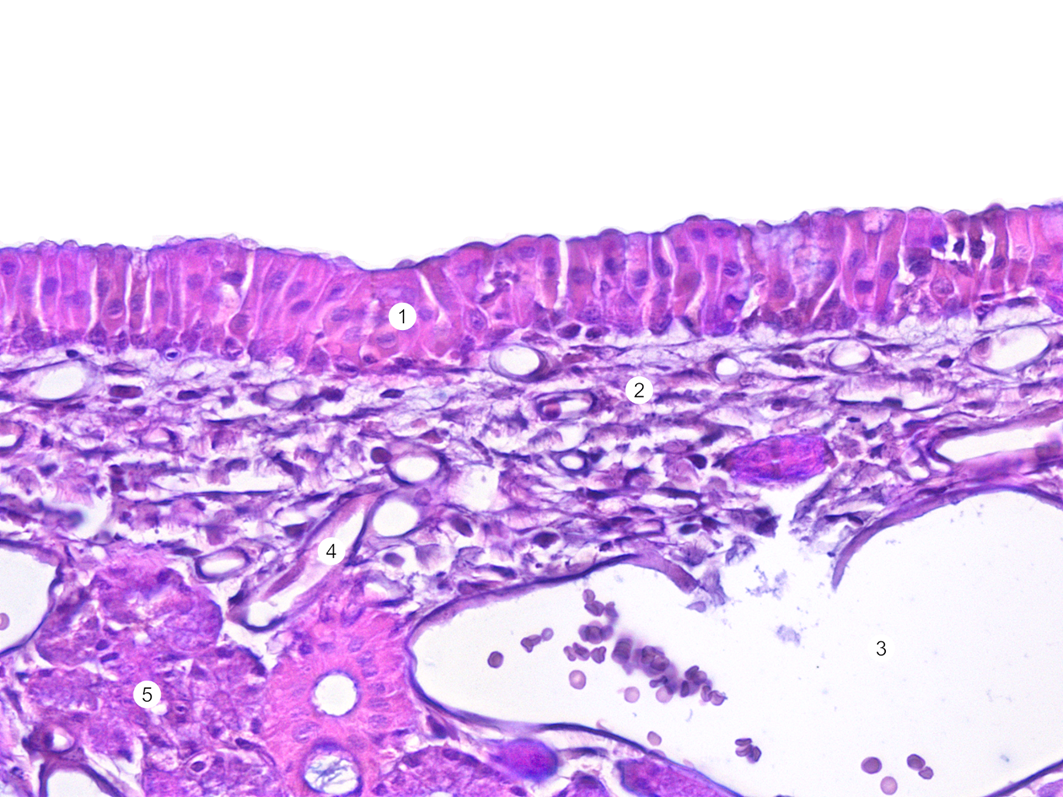

Препарат 1. Обонятельная выстилка. Однослойный многорядный мерцательный эпителий. В подэпителиальной соединительной ткани расположены концевые отделы обонятельных желез, кровеносные сосуды и пучки немиелинизированных нервных волокон обонятельного нерва. Слизь, секретируемая обонятельными железами, покрывает поверхность обонятельной выстилки слоем толщиной 60 мкм. 1 — обонятельный эпителий. 2 — собственный слой слизистой оболочки носа. 3 — кровеносный сосуд. 4 —лимфатический сосуд. 5 — боуменова железа. Препарат кафедры гистологии, цитологии и эмбриологии Казанского ГМУ.